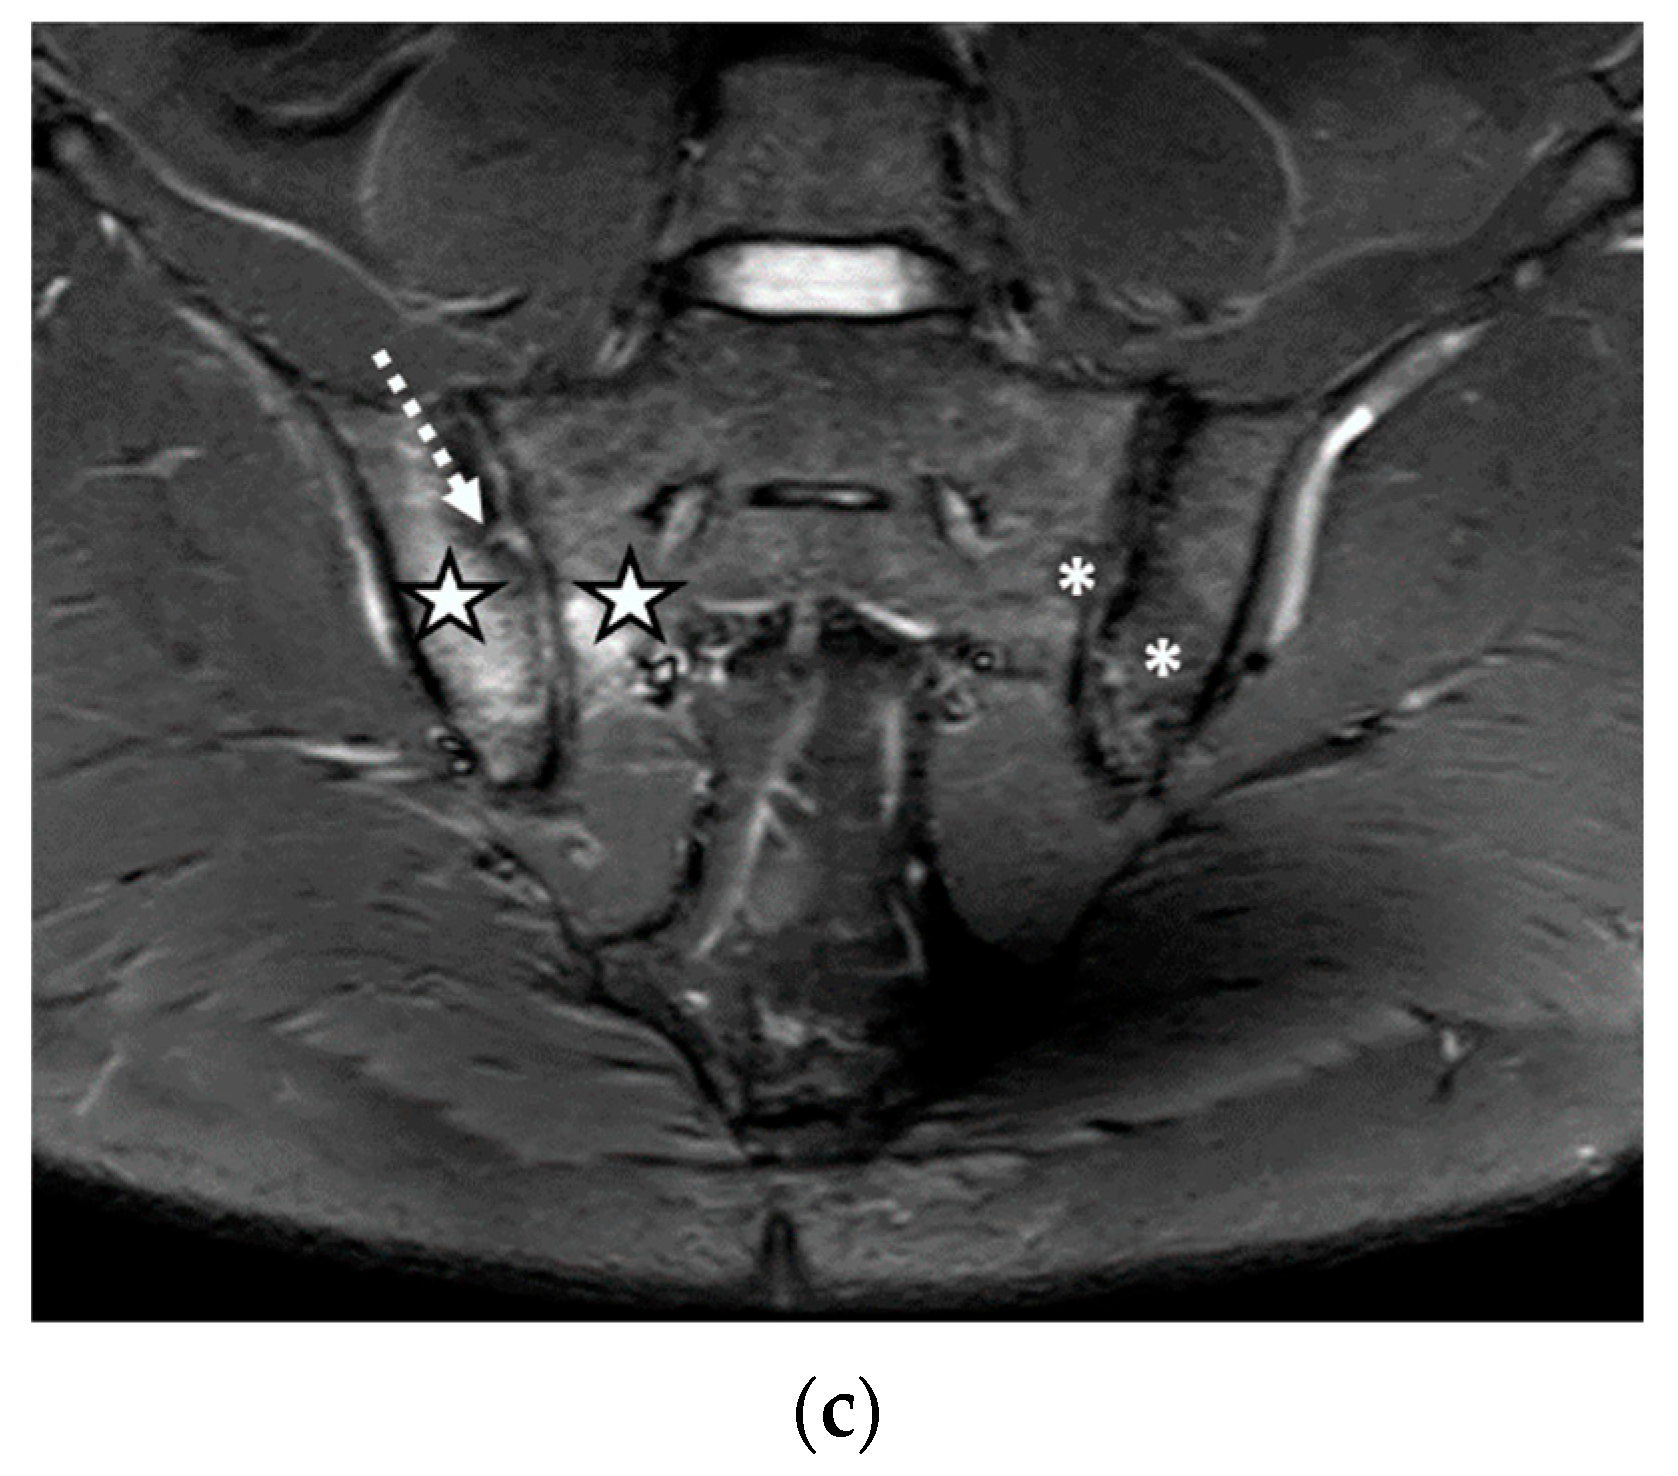

We evaluated 68 sacroiliac joints. The prevalence of MRI-detected abnormalities is presented in Table 2. The results of the SR were considered as the reference data. Inflammatory and structural changes were detected on the MRI sequences of the sacroiliac joints. The most frequently encountered inflammatory change, both on the left and right sacroiliac joint, was the presence of bone marrow edema (44.11–58.82%), followed by enthesitis (17.64–26.47%) and synovitis (11.76–17.64%). Regarding structural changes, the most prominent was subchondral sclerosis (50–59.37%), followed by erosions (35.29–41.17%), joint space narrowing (38.23%), fat metaplasia (17.64–23.25%), and backfill (11.76–20.58%) (Figure 1, Figure 2 and Figure 3).

Figure 2.

The MRI scan of the sacroiliac joints indicated bilateral narrowing of the sacroiliac joint space, associated with bilateral subchondral sclerosis of the iliac bones (continuous arrow); bilateral fat metaplasia (asterisk), mostly affecting the iliac bones and the right part of the sacrum; backfill of the right sacroiliac joint space (arrowhead); diffuse bone marrow edema (discontinuous arrow), affecting the sacrum and the left iliac bone: (a) T1-weighted sequence; (b) T2-weighted sequence (without fat suppression); (c) STIR sequence.